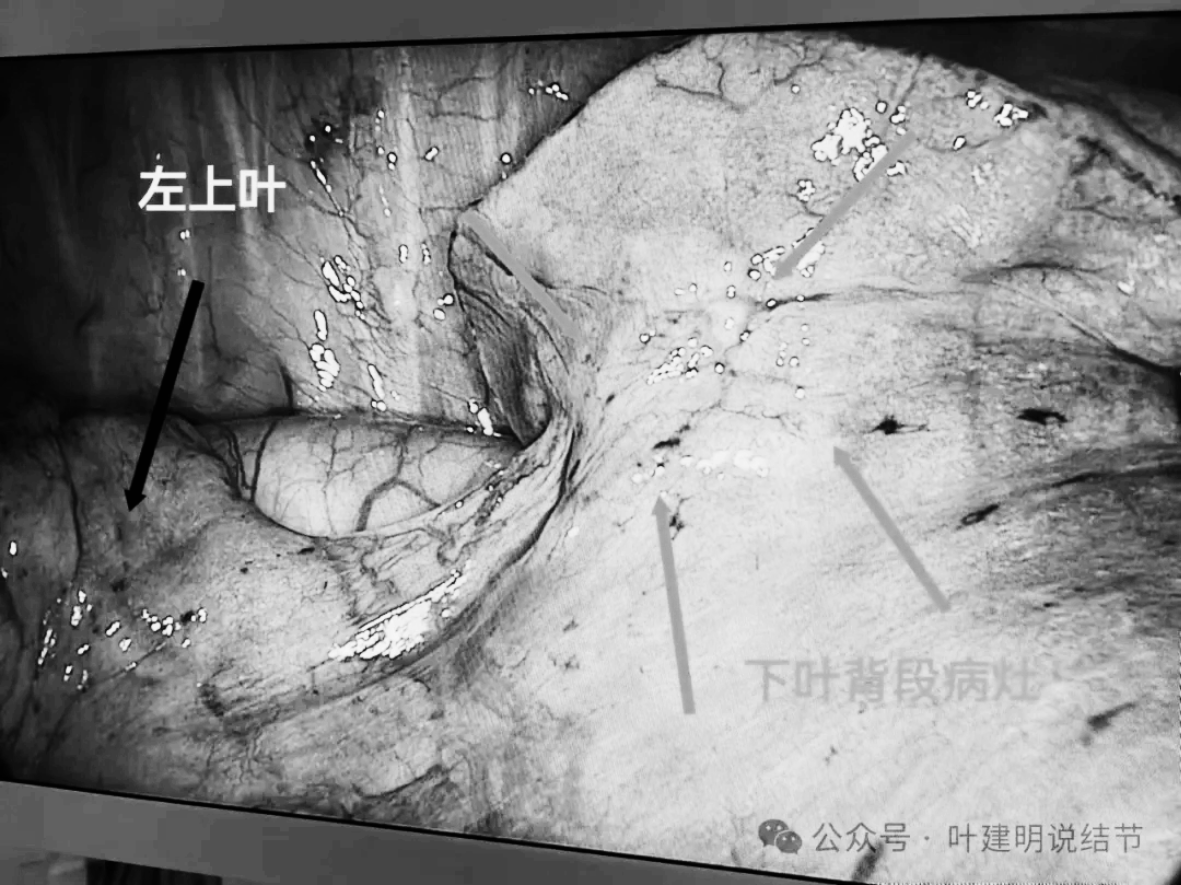

患者入住杭州市第一人民医院胸外科,由叶建明团队安排手术。做了单孔胸腔镜下左下叶背段切除加淋巴结采样。

标本镜下观,CT上紧贴主动脉壁,其实进胸后并没有侵犯到主动脉壁的,肺萎陷后就脱开的。病灶表面胸膜有皱缩,质较硬。

背段切除后胸内的样子。